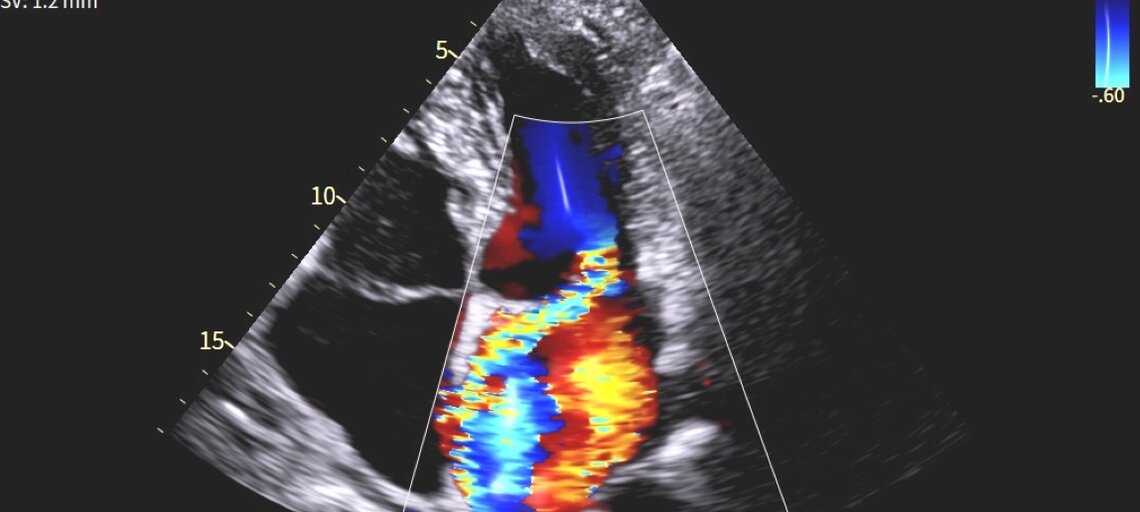

L’insufficienza mitralica (o rigurgito mitralico) è una malattia della valvola mitrale. Durante la contrazione del ventricolo sinistro, i lembi valvolari non si chiudono completamente e una parte del sangue rifluisce nell’atrio sinistro.

- Ecocardiogramma con Doppler (ecocolordoppler): esame di riferimento per quantificare il rigurgito, identificarne la causa e valutarne l’impatto su ventricolo e atrio sinistri.